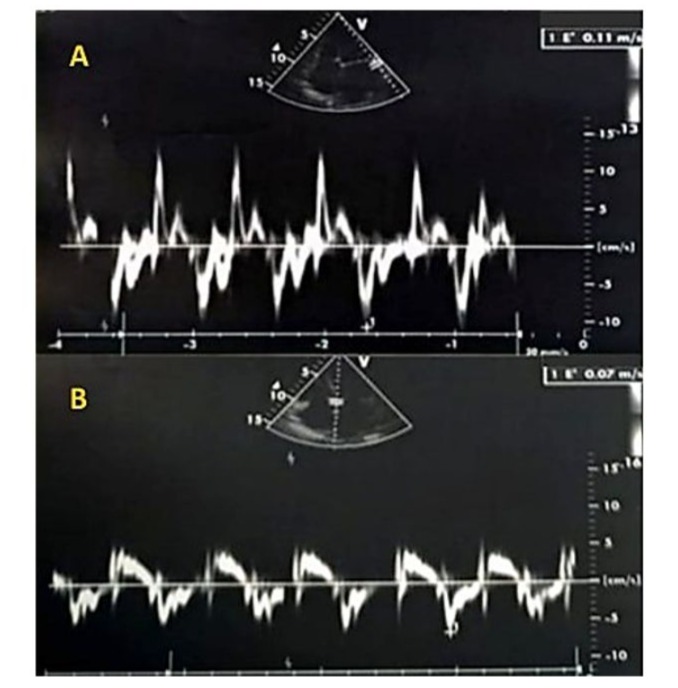

Figure 4: Tissue Doppler imaging (TDI) at the mitral annulus was performed using a 4-chamber view, minimizing filters and gains, and placing the sampling window at the lateral annulus (A) or the septal annulus (B). The TDI recording showed a positive systolic wave followed by a single diastolic Ea wave at 7 cm/s lateral, (A) and 11 cm/s septal, (B), with no Aa wave due to atrial fibrillation. The absence of significant reduction in the Ea wave indicates normal flow, as in healthy individuals, the Ea wave is typically greater than 8 cm/s